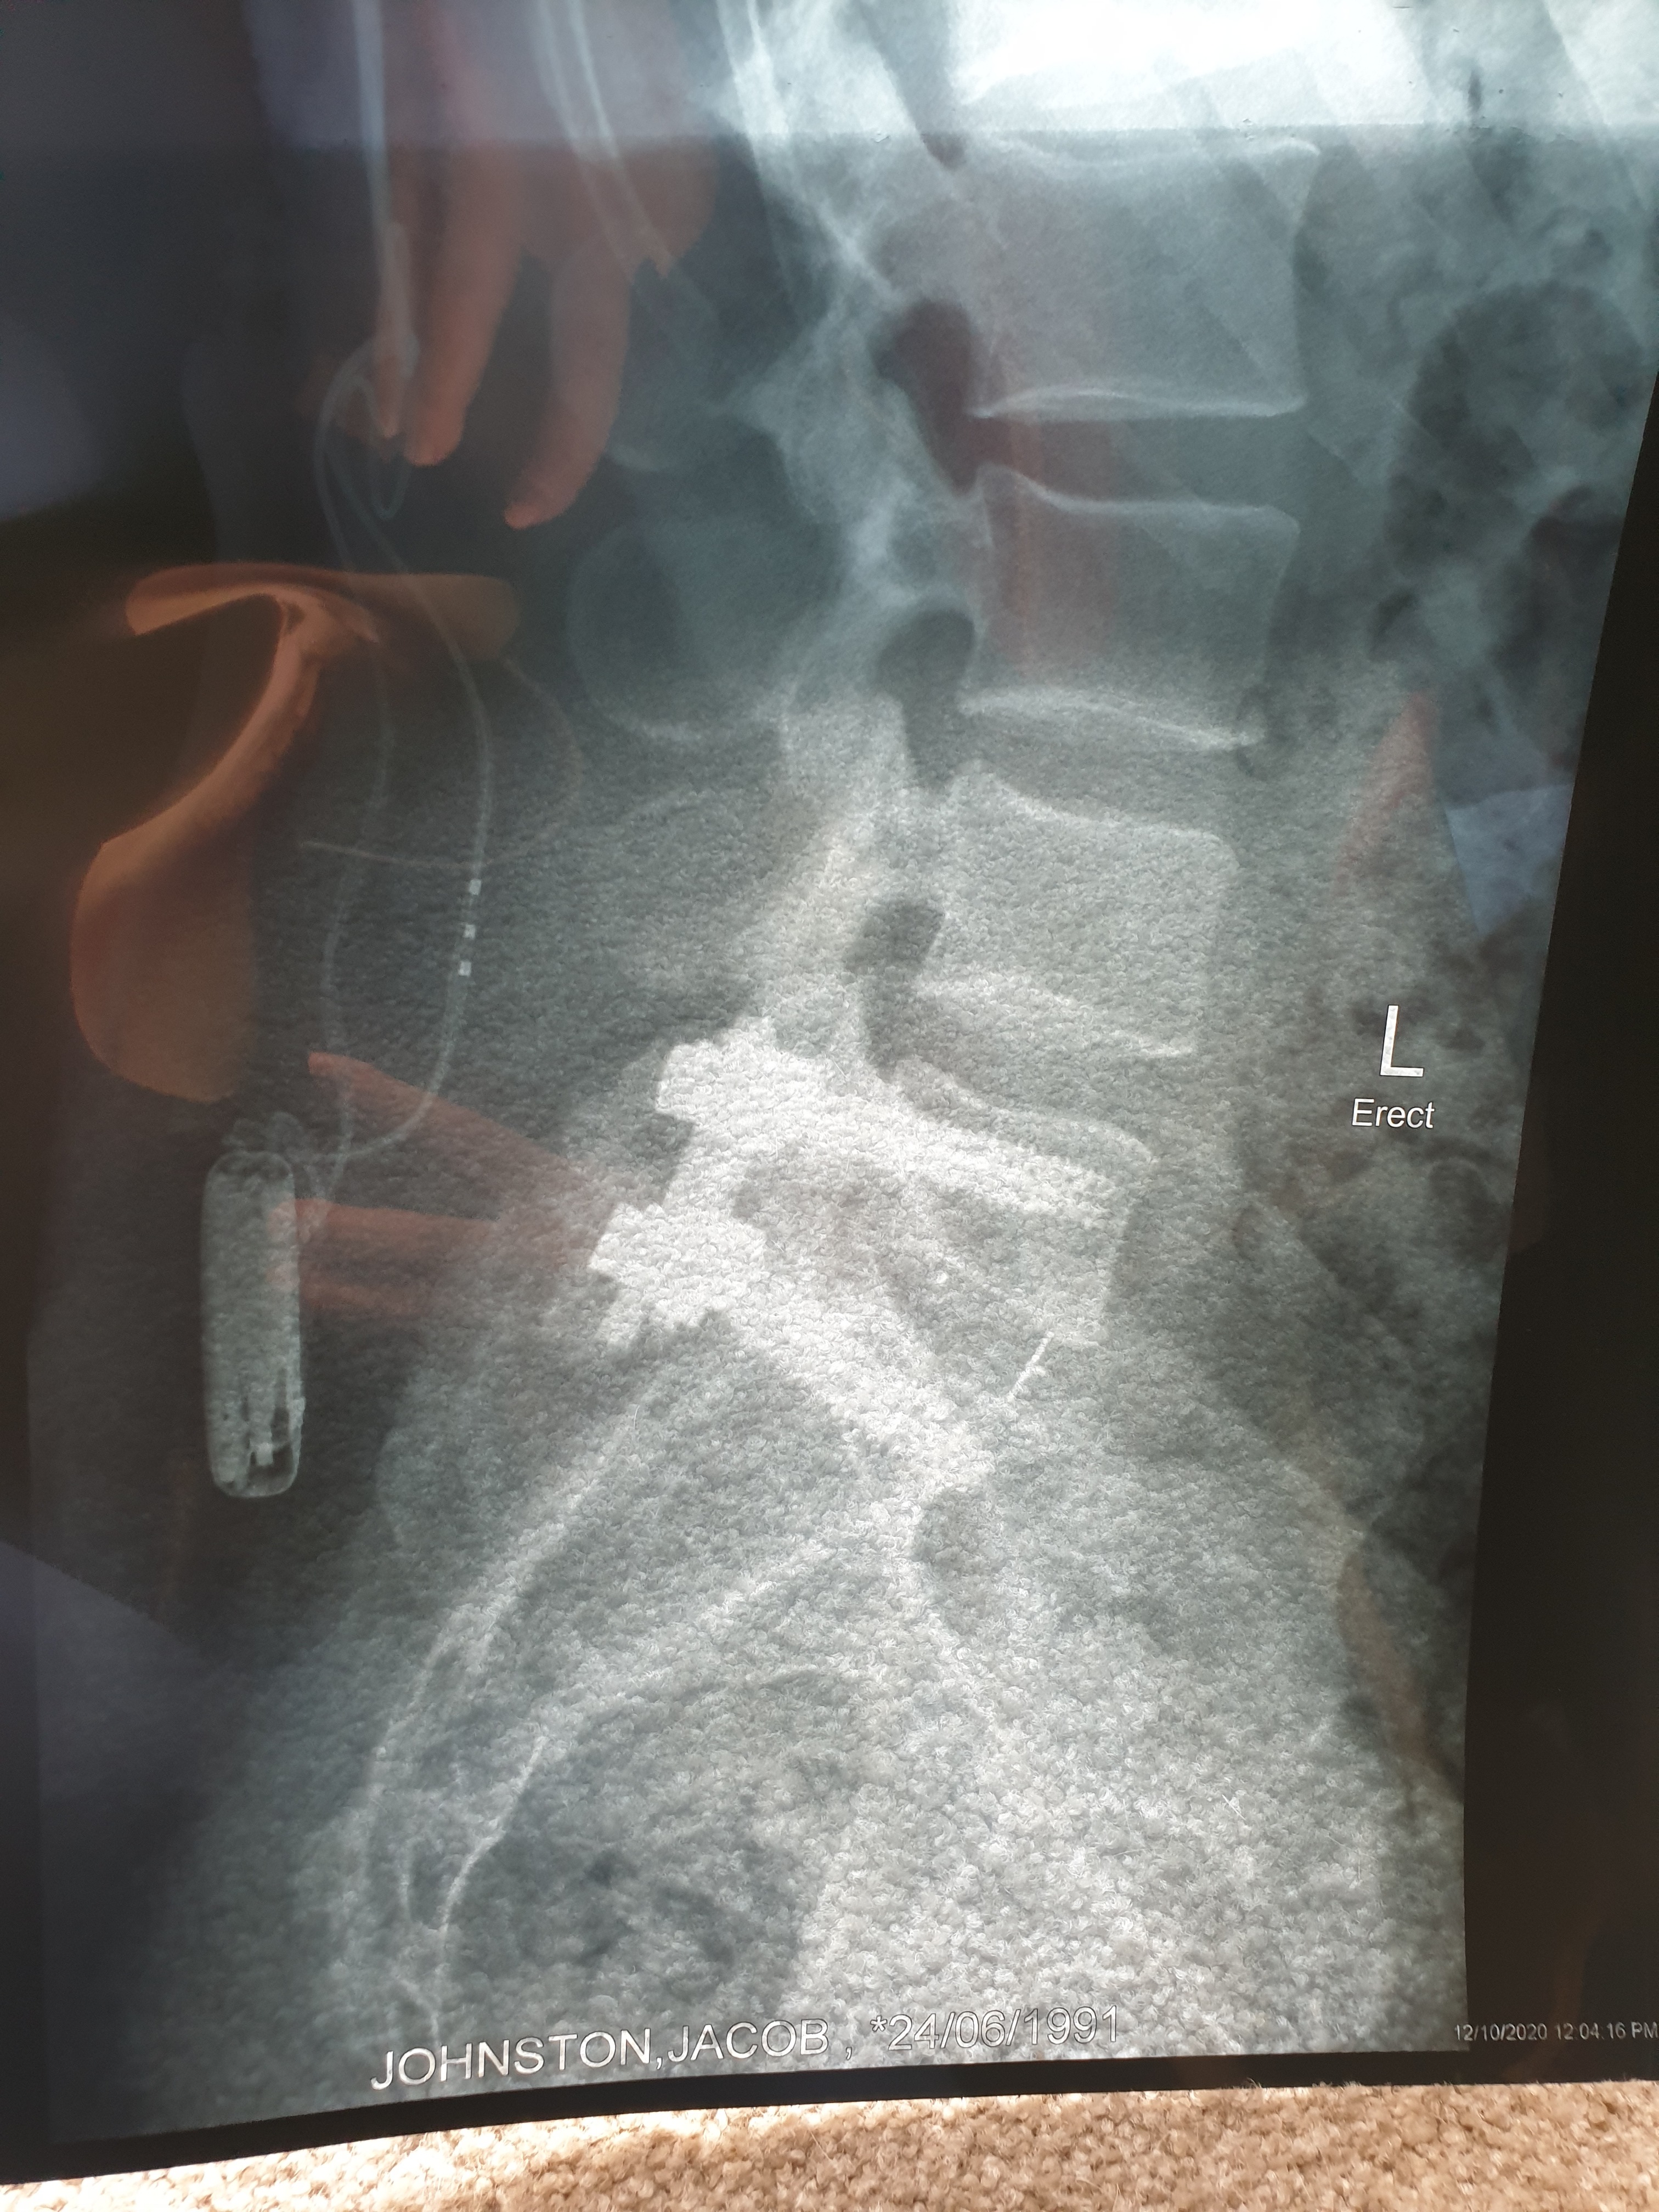

In October 2017, my husband Jake suffered a workplace injury. Since then, he has endured nine spinal surgeries and today, he lives as an incomplete paraplegic (limited use of his right leg).